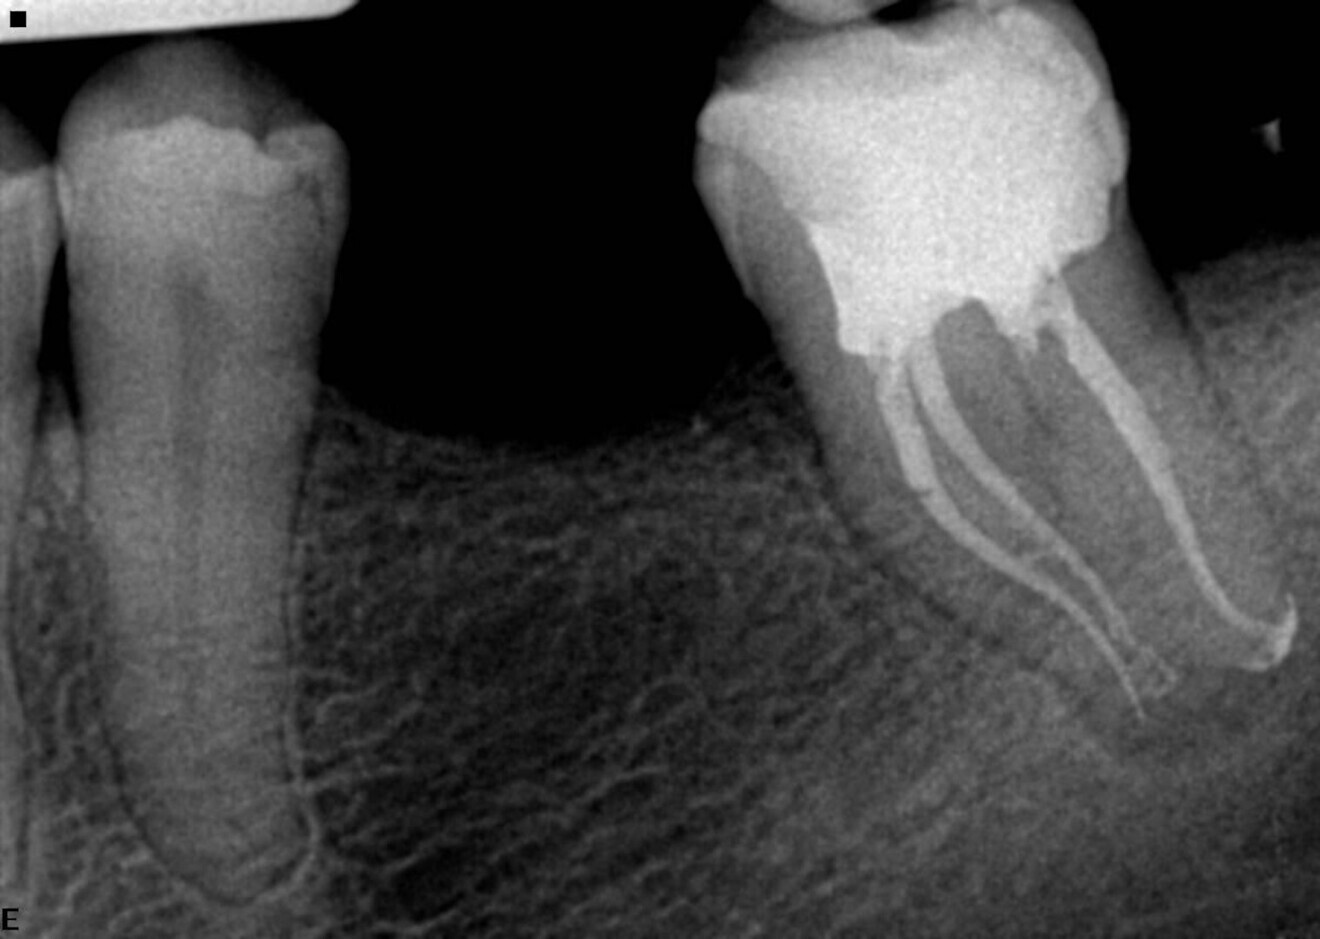

Maxillary second molars are in my opinion one of the most challenging teeth to treat because of their position and unpredictable anatomy. In this example case, the patient was referred for irreversible pulpitis (Fig. 5). Looking at the preoperative radiograph, we can see the curvature of especially the mesial and palatal root canals. The sequence used was as described before, starting with the 25/0.08 Traverse orifice opener as deep as it goes and just above the curve, followed by a 8 K-File for working length determination and the 13/0.06 Traverse file used to working length in all canals. During the use of the 13/0.06 Traverse file, I did not feel much resistance, so I decided to go ahead with the 0.06 taper sequence. The next file was the 20/0.06 ZenFlex, followed by the 25/0.06 ZenFlex file. Personally, I believe in apical enlargement, and for that reason, I used the 30/0.04 ZenFlex file as the final enlargement file in this case. I used a medium cone as the master cone and achieved 3D sealing of the system (Fig. 6). Of course, I performed complete chemical preparation, according to my sequence, during the procedure.

Fig. 5

Fig. 6